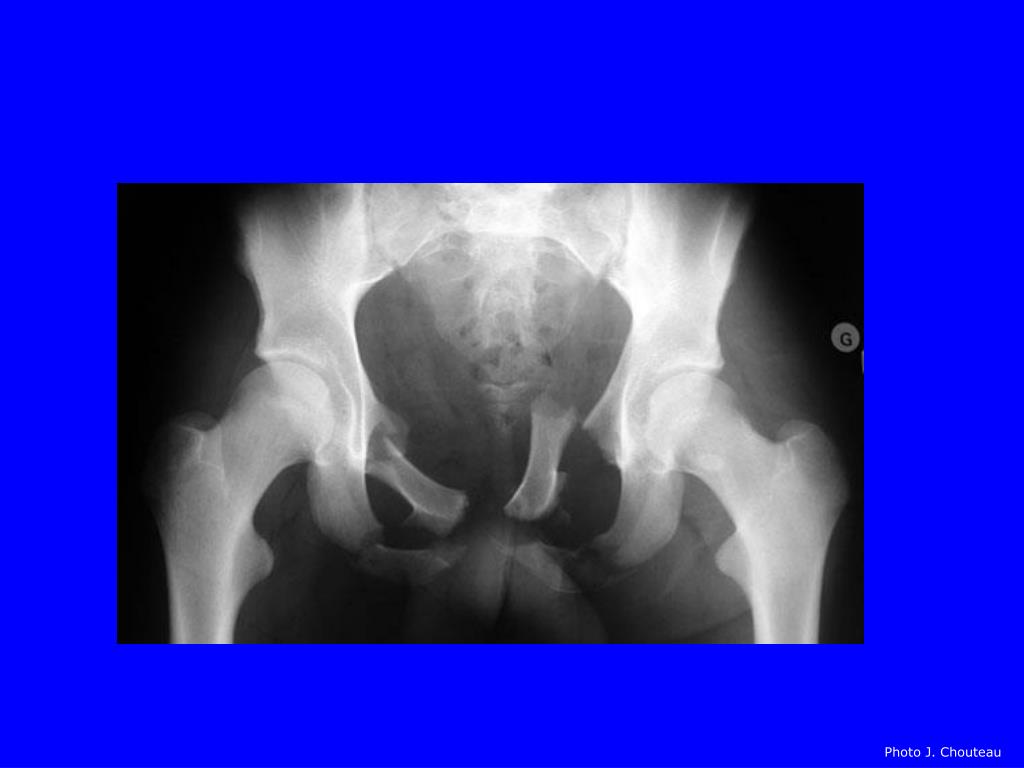

Fracture De Bassin . Le bassin est constitué de 3 structures osseuses : Dans cet article, on vous dit tout sur les fractures du bassin. Les fractures du bassin du sujet mûr, touchant plus volontiers les femmes, en raison de l'ostéoporose, et qui. Accident de voiture, de deux roues, chute violente, ou simplement de sa. L’iliaque, le sacrum et le pubis. Une rupture osseuse très douloureuse. Définition et types de fracture du bassin. Les fractures du bassin constituent la 3ème cause de mortalité lors d’accidents de la voie publique et ne sont précédées que par les traumatismes. | quelles sont les causes d’une fracture du bassin ? Il existe trois grandes catégories de fractures du bassin suivant le contexte : | quels sont les symptômes d’une fracture du bassin ?

| quelles sont les causes d’une fracture du bassin ? Les fractures du bassin constituent la 3ème cause de mortalité lors d’accidents de la voie publique et ne sont précédées que par les traumatismes. Le bassin est constitué de 3 structures osseuses : Une rupture osseuse très douloureuse. Les fractures du bassin du sujet mûr, touchant plus volontiers les femmes, en raison de l'ostéoporose, et qui. Définition et types de fracture du bassin. | quels sont les symptômes d’une fracture du bassin ? Accident de voiture, de deux roues, chute violente, ou simplement de sa. Il existe trois grandes catégories de fractures du bassin suivant le contexte : Dans cet article, on vous dit tout sur les fractures du bassin.

Fracture De Bassin Les fractures du bassin constituent la 3ème cause de mortalité lors d’accidents de la voie publique et ne sont précédées que par les traumatismes. Accident de voiture, de deux roues, chute violente, ou simplement de sa. | quels sont les symptômes d’une fracture du bassin ? Le bassin est constitué de 3 structures osseuses : Dans cet article, on vous dit tout sur les fractures du bassin. L’iliaque, le sacrum et le pubis. | quelles sont les causes d’une fracture du bassin ? Il existe trois grandes catégories de fractures du bassin suivant le contexte : Les fractures du bassin constituent la 3ème cause de mortalité lors d’accidents de la voie publique et ne sont précédées que par les traumatismes. Les fractures du bassin du sujet mûr, touchant plus volontiers les femmes, en raison de l'ostéoporose, et qui. Définition et types de fracture du bassin. Une rupture osseuse très douloureuse.